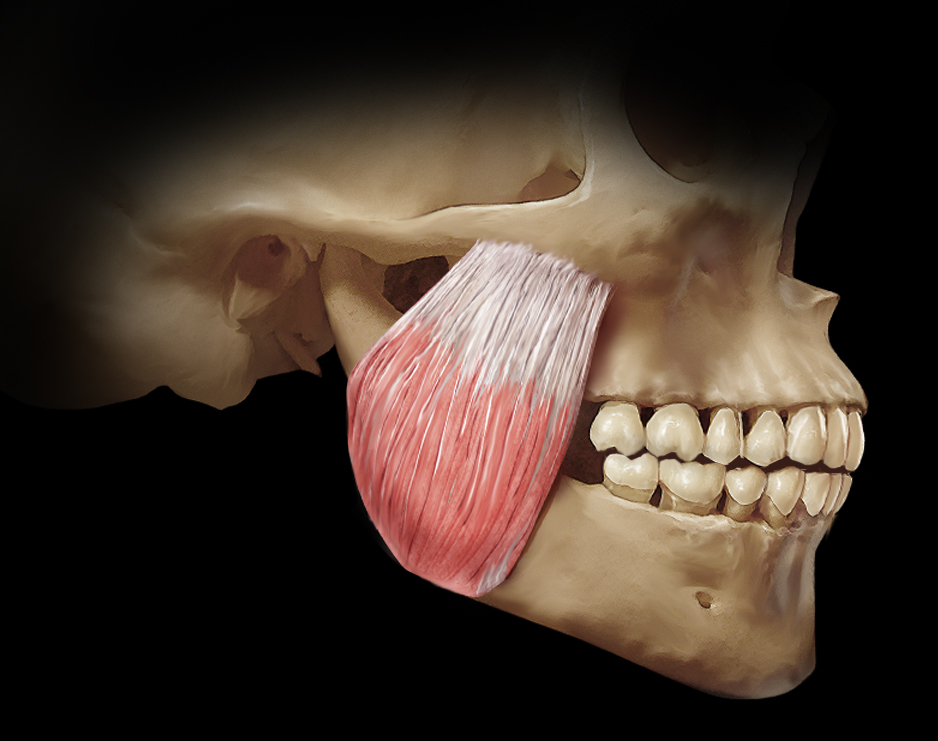

Eight muscles should be in every dentist's frame of reference. The four most significant of these muscles can be evaluated with relative ease: the masseter (Figure 5), temporalis (Figure 6), medial pterygoid, and lateral pterygoid (Figure 7). The digastric muscle, sternocleidomastoid, trapezius, and splenius capitis can be problematic to occlusion and TMJ issues, but they do not need to be examined at the outset unless TMJ dysfunction is discovered.

Fig 5. Masseter muscle.

Figure 5

Fig 6. Temporalis muscle.

Figure 6